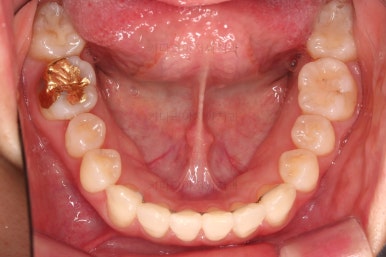

4. 마무리

철사교정과 마찬가지로 앞니쪽에 유지장치를 구성하고 치료를 종료합니다.

매우 가지런해졌고요.

맞물림도 좋아졌고, 중앙선도 잘 맞춰졌습니다.

부산인비절라인 전후 비교해 보겠습니다.

입매를 유지하면서 비발치이더라도 입이 더 나오지 않게 마무리 했고요.

가지런한 느낌 좋고, 중앙선이라던지 교합도 좋아졌습니다.